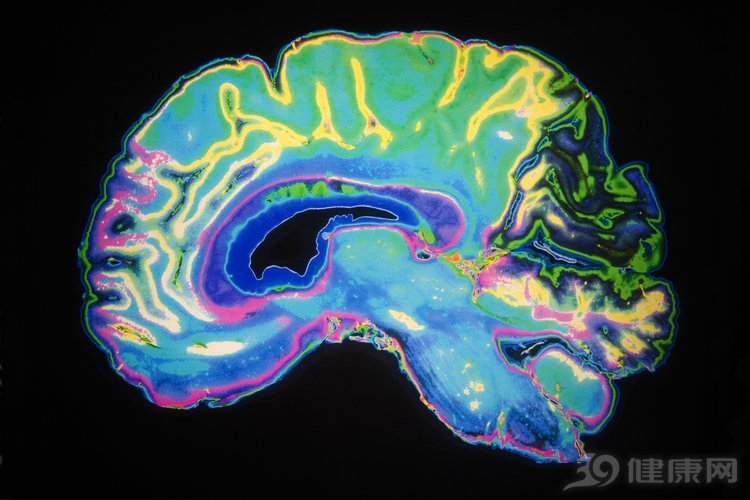

人类的生活和工作想要正常运转,都离不开大脑的指挥,如果人未老,脑先衰,对每个人都是沉重的打击。设想下,如果工作中经常忘东忘西、丢三落四,毫无想法和创意,肯定会引发领导的责骂,甚至很可能会有失业的危险。那么,生活中我们如何护脑呢?有什么护脑的好方法能让年轻人创意多多吗?